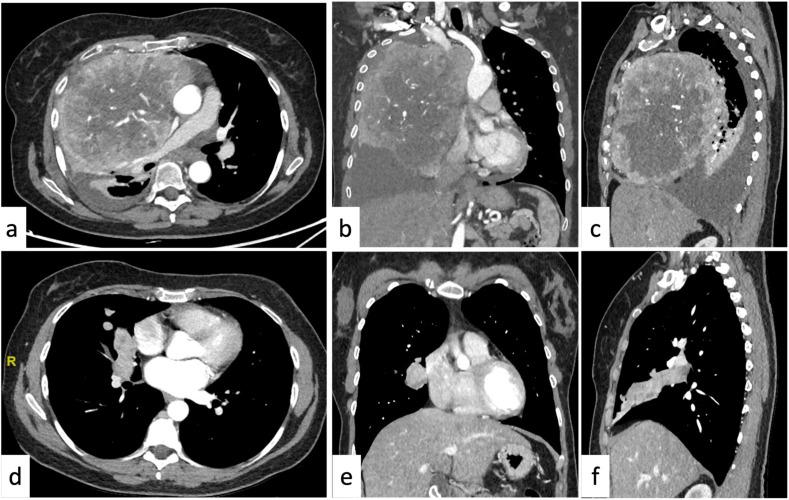

This review has the purpose of illustrating schematically and comprehensively the key concepts for the beginner who approaches chest radiology for the first time. The approach to thoracic imaging may be challenging for the beginner due to the wide spectrum of diseases, their overlap, and the complexity of radiological findings. The first step consists of the proper assessment of the basic imaging findings. This review is divided into three main districts (mediastinum, pleura, focal and diffuse diseases of the lung parenchyma): the main findings will be discussed in a clinical scenario. Radiological tips and tricks, and relative clinical background, will be provided to orient the beginner toward the differential diagnoses of the main thoracic diseases.